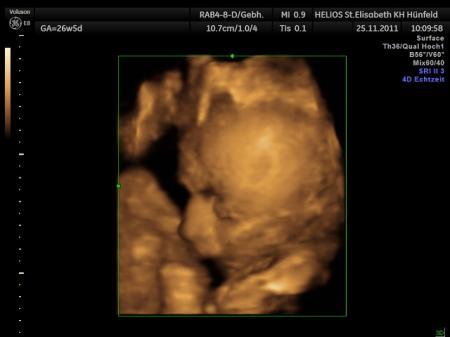

Hallo ihr lieben, endlich konte ich gestern meine kleine Nudel auch mal in 3D betrachten :), nur leider hat sie ihre Nase gegen mein Mutterkuchen gedrückt, so das wir erstmal Schwierigkeiten hatten ein schönes Foto von ihr zu bekommen. Dafür habe ich jetzt ganz viele süße Fotos von meiner kleinen mit plattgedrückter Nase Ansonsten ist alles super, ihr gehts gut und wiegt jetzt 1098g bei ca. 35cm

Bild zu Endlich auch 3D - Forum für Februar - Mamis